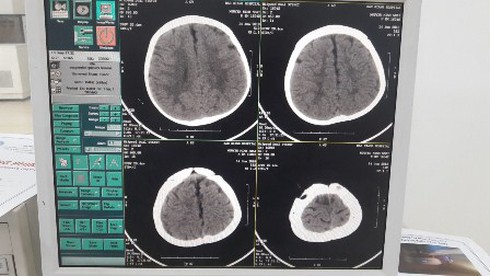

Hình ảnh sọ não sau can thiệp |

Nếu không thành công thì khi đó bệnh nhi sẽ phải chịu một cuộc phẫu thuật cũng như những rủi ro trước, trong và quá trình hậu phẫu là rất nặng nề, bên cạnh đó công tác gây mê hồi sức cho trẻ dưới 12 tháng tuổi cũng là một thách thức không nhỏ kể cả đối với các bệnh viện tuyến trung ương.